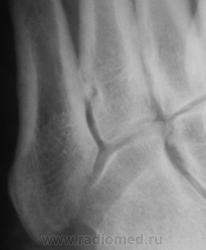

Вы правы, сверху упала "железяка".

Может это сейчас от меня "гипердиагностика попрет", но можно заподозрить отрыв косого аддуктора большого пальца с костным фрагментом.